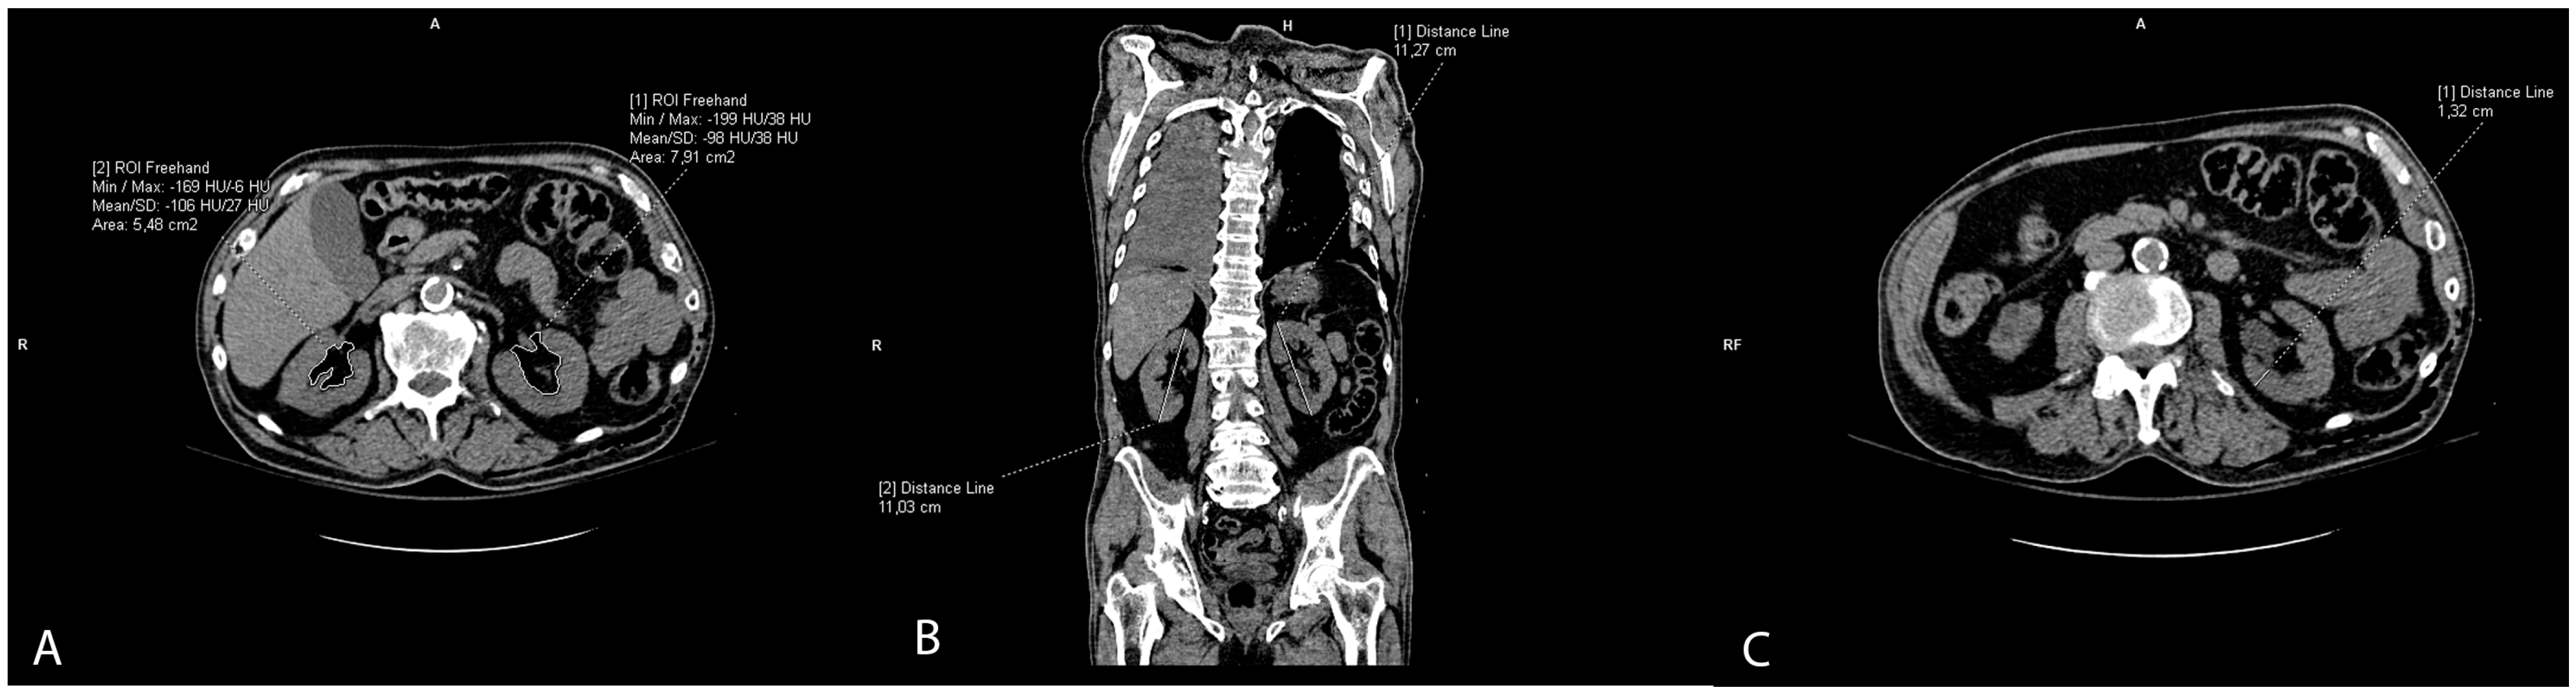

2.5. Renal Sinus Fat Accumulation and Renal Imaging Parameters

The slices of the renal hilus of each kidney containing the largest amount of sinus fat were used to measure a renal sinus fat area in cm2, representing ectopic renal sinus fat accumulation. The sinus fat surface area was traced manually and identified by its low-density fatty content with a negative HU (Figure 3A). The length of the kidney was measured on the coronal reconstructions as the longest craniocaudal diameter of each kidney (Figure 3B). Renal parenchymal thickness was measured at the hilar level on axial scans (Figure 3C).

Figure 3. Representative CT scans showing renal parameter volume measurements: renal sinus fat area (A), length of the kidney (B), and renal parenchymal thickness (C).